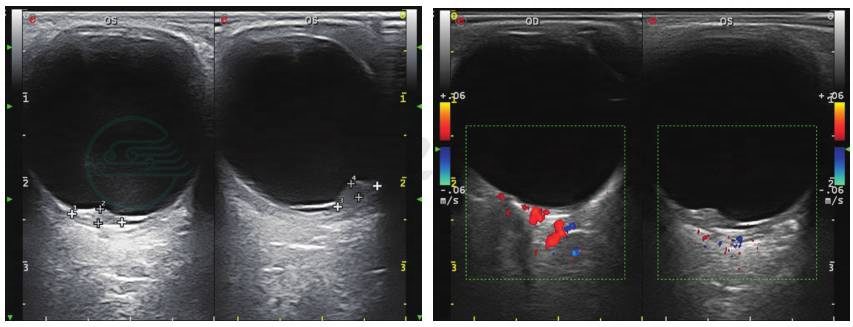

图4 眼部彩超检查

视盘颞下方玻璃体腔内可探及一边界清晰的隆起实性病变,其内回声不均匀,未见血流信号;其表面可探及与其相连的带状回声,其上可见血流信号,考虑球内占位伴渗出性视网膜脱离。